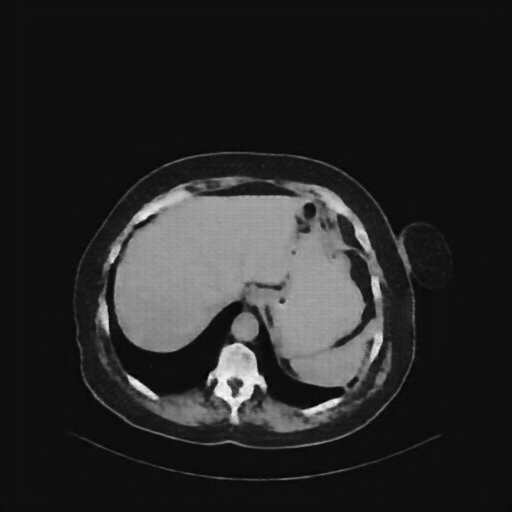

Original NATIVE CT scan (input)

Full window (WL 1023.5, WW 4095 β Low β1024, High +3071)

Actual HU range: [-160.0, 240.0]

Lung window (WL -600, WW 1500 β Low β1350, High +150)

Actual HU range: [-160.0, 150.0]

Mediastinum window (WL 40, WW 400 β Low β160, High +240)